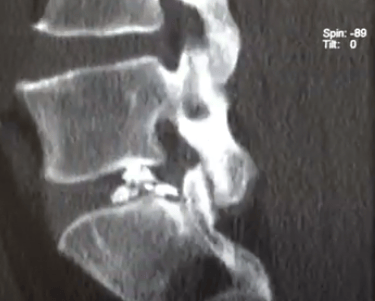

An intriguing case involved severe herniation and disc rupture between L4 and L5 vertebrae, causing intense pain. Opting out of surgery, the patient chose to try Discogel. Due to severe foraminal stenosis from the extruded disc, the Discogel injection was cautiously prolonged to one hour. Post-injection CT scan revealed effective penetration into fragmented disc components in the narrowed foraminal space.

The patient's pain gradually diminished after 4-5 weeks, and complete relief was achieved after several months.

The first image is six months post-injection, and the second image is three years post-injection."